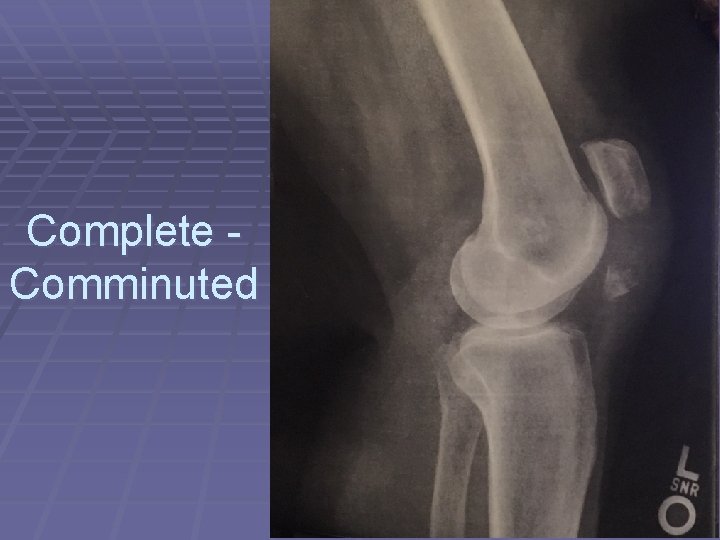

Complete - Comminuted fracture

Complete - Comminuted

Complete Comminuted

Complete, Open - Comminuted